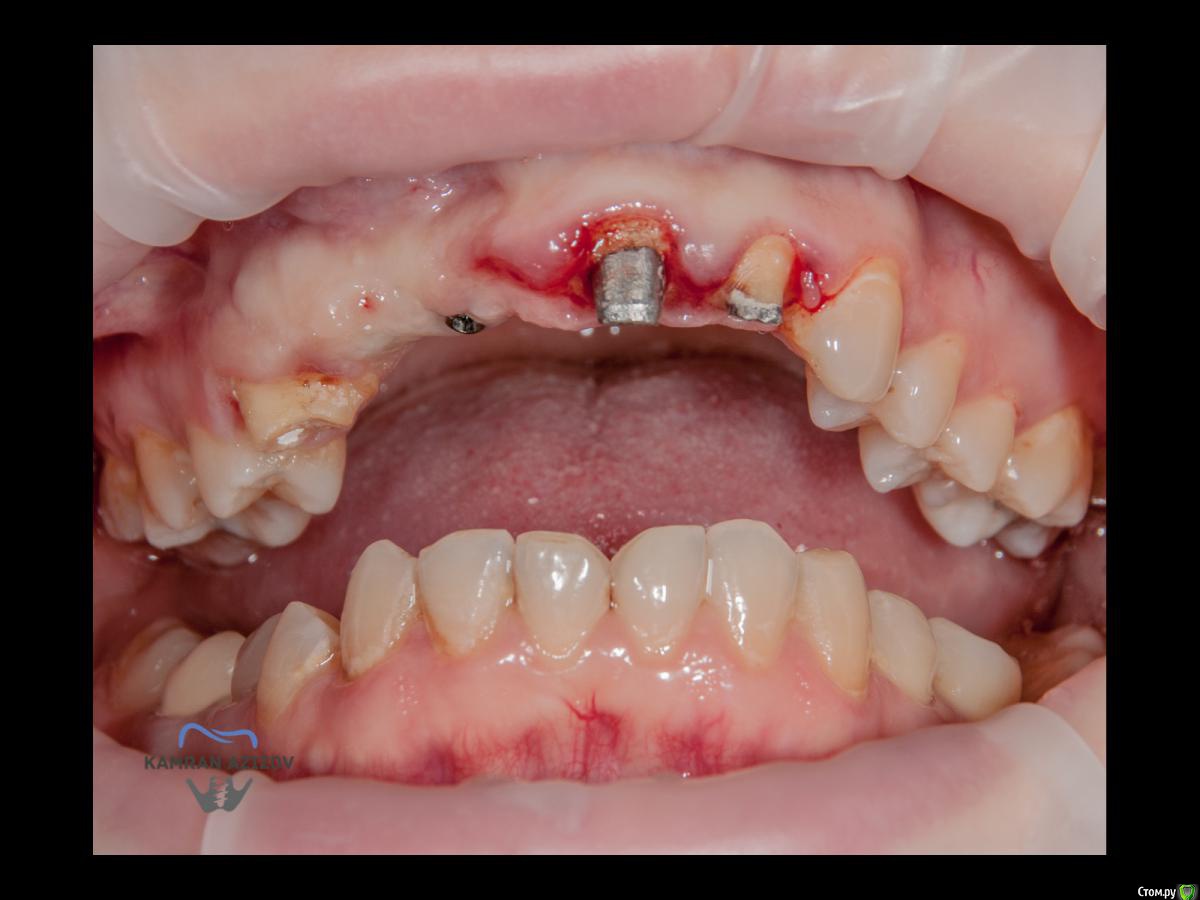

kamranchick Опубликовано 6 апреля, 2019 Поделиться Опубликовано 6 апреля, 2019 (изменено) Хай Гайсдавно ничего не комментировал и не выкладывал, что то настроения не было, да и муза не посещалаСитуация следующаяпришла пациентка, жалобы на неприятный запах из рта, сначала не понял что за хрень, ну как распилил мост понял че к чему... халтура.Ну и по кейсуУдаление клыка и 2ки, через 2 месяца навигация, имплантация + Шашлыки по карлоссу, смена формиков, временное протезирование. только мягкие ткани, Изменено 6 апреля, 2019 пользователем kamranchick 7 1 Ссылка на комментарий

jm3300 Опубликовано 6 апреля, 2019 Поделиться Опубликовано 6 апреля, 2019 А 12- на винтовой? Ссылка на комментарий

kamranchick Опубликовано 7 апреля, 2019 Автор Поделиться Опубликовано 7 апреля, 2019 Тут все на винтовой фиксации Ссылка на комментарий

Nazim_NV86 Опубликовано 7 апреля, 2019 Поделиться Опубликовано 7 апреля, 2019 Пятый Без пина шаблон не держался? Ссылка на комментарий

kamranchick Опубликовано 8 апреля, 2019 Автор Поделиться Опубликовано 8 апреля, 2019 ТакУважаемый Петр) начнем по порядку1. пациентка отказалась от нее, как только не уговаривал ее, просто танцы с бубном были)2. после удаления клыка сразу ушел хиленький резец, делать мост 14-21-22 как то страшновато было из-за протяженности дефекта3. 1.4 зуб жалко было удалять, зачем удалять еще один зуб если так и так 2 имплантата, ну как вариант можно было бы, было бы легче позиционировать имлпнтататы4. в позиции 1.1 был большой резцовый канал, не захотелось проводить какие то манипуляции вокруг него и с ним, ну как то так)) Ссылка на комментарий

kamranchick Опубликовано 8 апреля, 2019 Автор Поделиться Опубликовано 8 апреля, 2019 Пятый Без пина шаблон не держался? держался) но сделали на всякий случай) Ссылка на комментарий

kamranchick Опубликовано 9 апреля, 2019 Автор Поделиться Опубликовано 9 апреля, 2019 kamranchick11з консоль, или это единая конструкция?13-12 с консолью на 11 Ссылка на комментарий